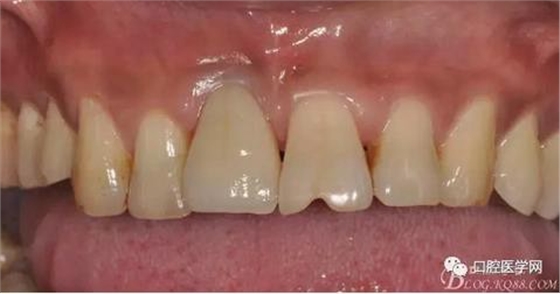

圖19 口內(nèi)修復(fù)基臺(tái)正位照

圖20 口內(nèi)修復(fù)基臺(tái)正位照